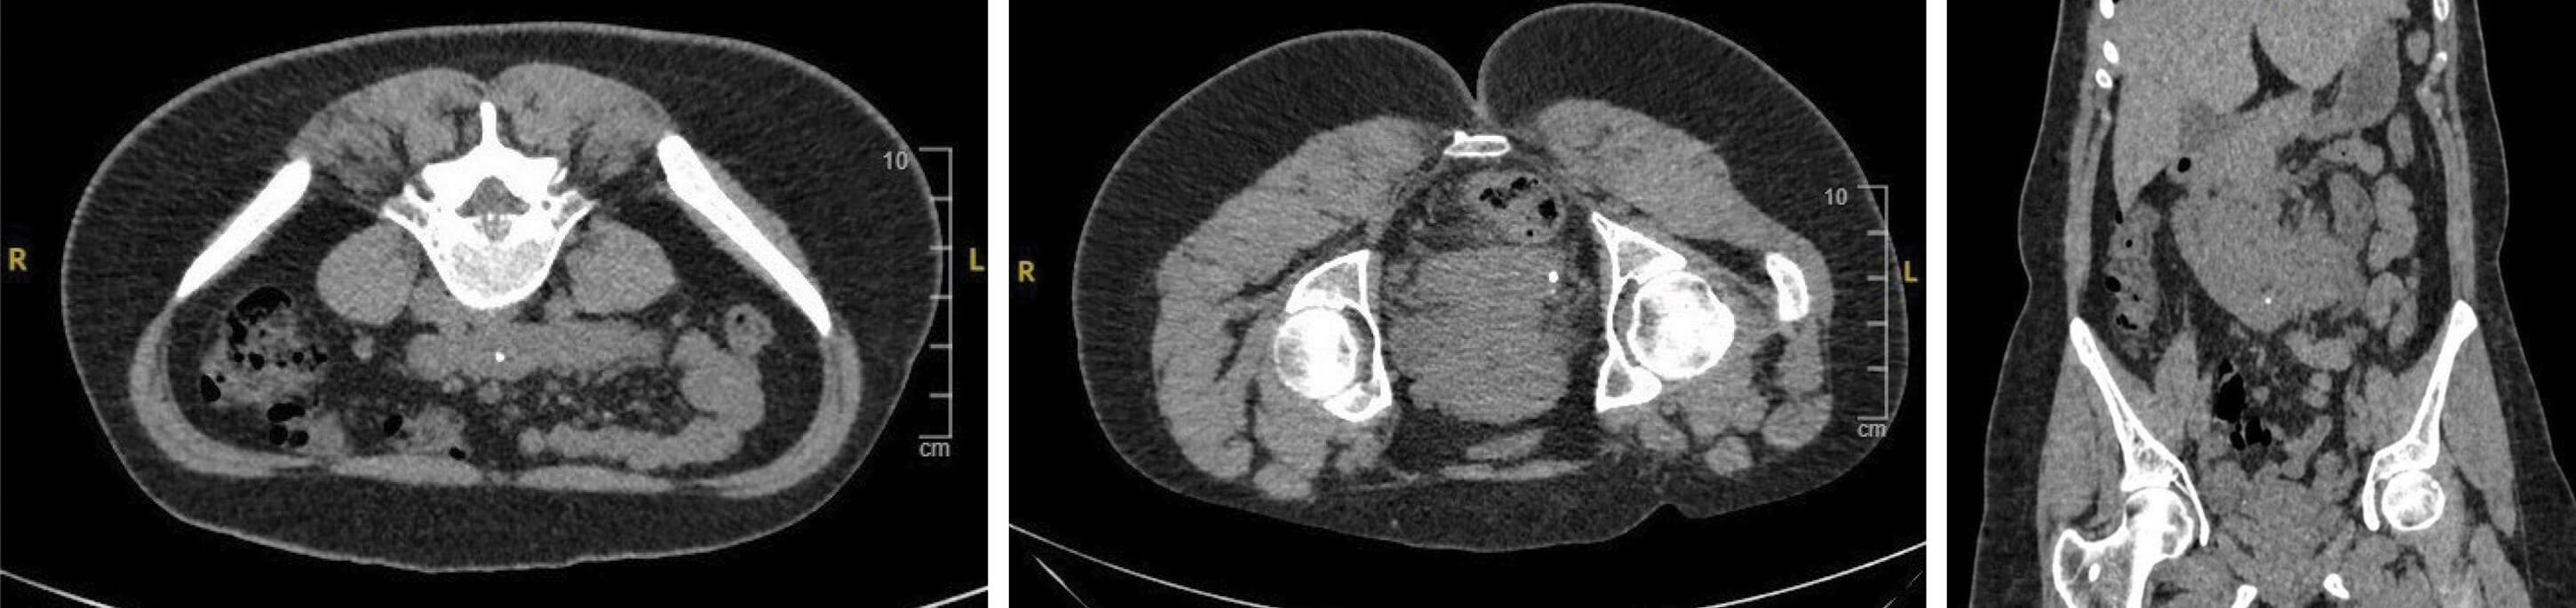

Figure 1.

- A 26-year-old female presents to A&E with loin pain. What do the CT images in Figures 1 (left, centre and right) show?

Figure 4.

- Horseshoe kidney with a small stone in the renal pelvis and a ureteric stone.

- Horseshoe kidney has a population prevalence of 0.25%, being twice as common in men [1].